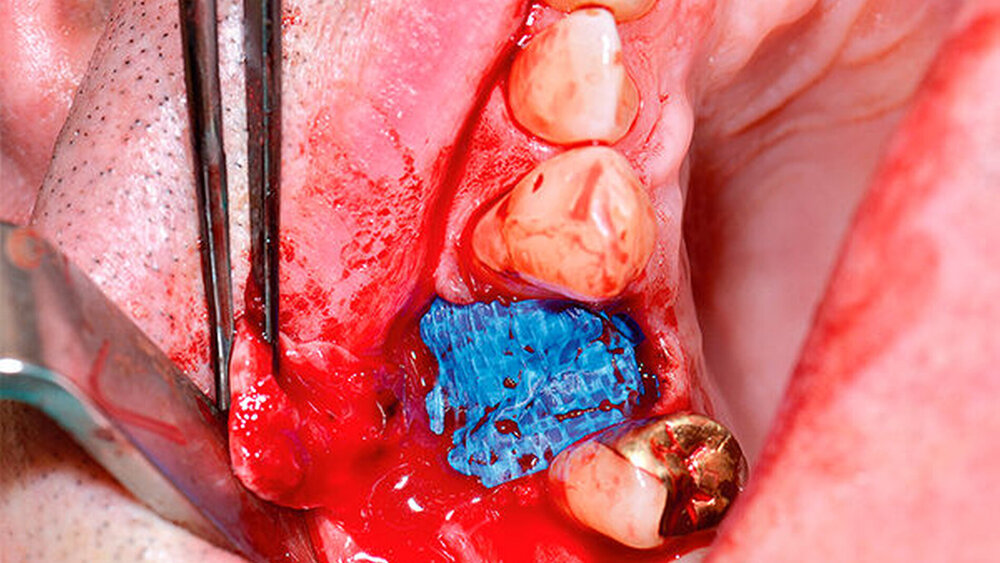

Der folgende klinische Fall dokumentiert die Behandlung eines 61 Jahre alten Patienten, der sich initial mit erheblichen Beschwerden an Zahn 14 vorgestellt hatte. Die radiologische Untersuchung (Abb. 1) ergab eine periapikale Aufhellung sowie eine insuffiziente Wurzelkanalbehandlung. Im Folgenden wurde die Krone entfernt und eine Revision der Wurzelkanalbehandlung durchgeführt. Im Rahmen der Revisionsbehandlung stellte sich eine Längsfraktur im Bereich der vestibulären Wurzel dar. Aufgrund der daraus resultierenden schlechten Prognose einer weitführenden konservierenden Therapie wurde der Zahn atraumatisch entfernt und die Alveole sorgfältig von Granula‧tionsgewebe und einem sich apikal befindenden Zystenbalg befreit (Abb. 2). Das gewonnene Gewebe wurde der histopathologischen Untersuchung zugeführt; dabei ergab sich das Bild einer radikulären Zyste. Aufgrund der latent vorhandenen Inflammation im Bereich der Alveole wurde auf eine sofortige Augmentation mit Knochenersatzmaterial im Sinne einer Ridge Preservation verzichtet. Die Alveole wurde konventionell mit einem Kollagenkegel und einer adaptierenden Naht versorgt. Nach Besprechung mit dem Patienten wurde eine implantatprothetische Versorgung geplant. In der ersten chirurgischen Phase (sechs Wochen nach der Extraktion) erfolgte ein horizontaler Alveolarkammaufbau mittels GBR-Technik unter Lokalanästhesie, um das abgebaute Knochengewebe wiederherzustellen und damit ein entsprechendes Implantatbett zu gestalten. Präoperativ zeigten sich vestibulär in regio 14 sowohl der Knochen als auch das Weichgewebe defizitär (Abb. 3). Im Rahmen der geplanten Augmentation erfolgte die Bildung eines lokalen Mukoperiostlappens in regio 14. Aufgrund der aus den vorhergegangenen operativen Eingriffen resultierenden Narbenzüge im OP-Gebiet wurde auf eine gängige Lappenextension über das Augmentationsgebiet hinaus verzichtet. Nach Lappenbildung konnte der wandige Defekt exploriert und intensiv mit physiologischer Kochsalzlösung gespült werden (Abb. 4). Im Anschluss erfolgten die Vorlage einer neuen nicht resorbierbaren Membran (permamem, botiss biomaterials, Zossen, Deutschland) sowie der Zuschnitt der Membran entsprechend der Größe des abzudeckenden Defekts (Abb. 5). Es folgte die Augmentation des wandigen Knochendefekts mit allogenem Knochenersatzmate‧rial (maxgraft spongiöse Granula, botiss biomaterials), das zuvor mit venösem Eigenblut des Patienten durchmischt worden war (Abb. 6 und 7). Danach wurde das Augmentat mit der vorgelegten nicht resorbierbaren Membran abgedeckt (Abb. 8). Der Wundverschluss erfolgte mittels horizontaler Matratzennaht und Einzelknopfnähten (Resolon 4.0/5.0, Resorba, Nürnberg, Deutschland) (Abb. 9). Die postoperativ angefertigte Halbseiten-Panoramaschichtaufnahme zeigte eine vollständige Augmentation der Defektregion (Abb. 10).